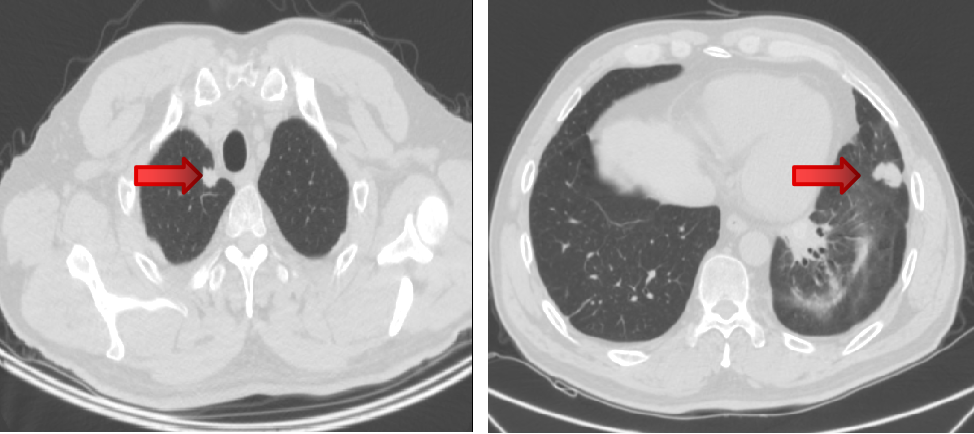

局部治疗(三):粒子植入

2021-10-29、2021-11-1 行CT引导下双肺转移灶放射性碘125粒子植入术。

局部治疗(四):粒子植入

2022-4-13、2022-4-15 行CT引导下双肺转移灶放射性碘125粒子植入术。

2022-4-21 肺转移组织基因检测。